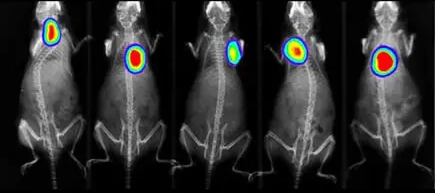

Metastaza nowotworu, znakowanie bioluminescencyjne: IVIS Spectrum CT